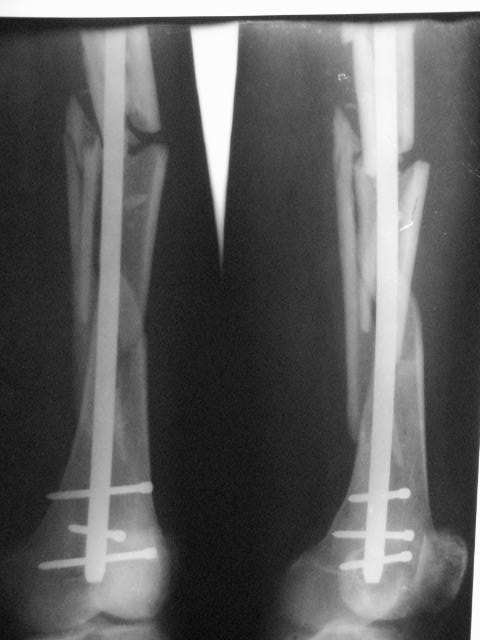

Открытый (2 В Каплан) многооскольчатый перелом левого бедра. Перелом межмыщелкового возвышения большеберцовой кости без смещения слева. Открытый (1 А Каплан) перелом с/3 -н/3 костей правой голени, перелом пяточной кости справа.На седьмые сутки выполнены операции:1. ЗИМО (статически, Chm-CHARFIX) левого бедра. 2. Остеосинтез стержневым аппаратом костей правой голени и пяточной кости. См. r-gr.На сегодня аппарат демонтирован, больной ходит с ограниченной нагрузкой.Смущает стояние отломков в верхней трети бедра (как то не задумались при планировании операции о реконструктивном или гамме штифте ) хватит ли этих двух винтов для стабильности?С Уважением Владимир Бахарев.

Длина проксимального отломка тут достаточна для использования любого диафизарного гвоздя, так что в этом отношении как раз все в порядке. Запас прочности, однако, тут для ранней полной нагрузки недостаточен, и даже с реконструкционным было бы немногим больше - дистальные винты те же 4,5 мм, а они у гвоздей ChM довольно хлипкие. Так что с нагрузкой тут лучше не спешить до уверенных признаков пластики на снимках.

Видна заметная наружная ротация центрального отломка. Если это не случайно сделали снимок, не выведя колено в нейтральное положение, то это типичное смещение, если делать синтез на тракционном столе с тазовой подставкой и промежностным упором. Стоило бы сделать снимок обоих тазобедренных суставов при одинаково уложенных коленных. Для этой же цели можно сделать и снимок в сгибании 90 градусов коленых и тазобедренных суставов, будет прямо видно

антеверсию шеек. Спасибо за презентацию непростого пациента.